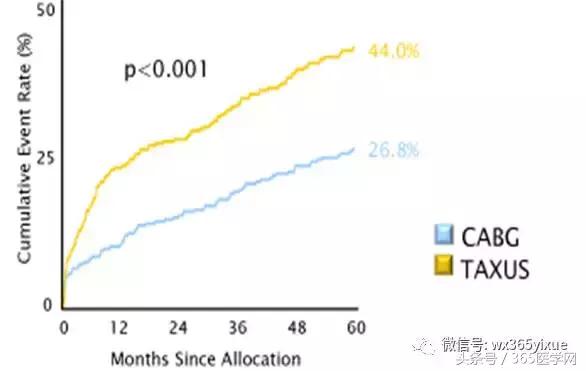

临床策略

CABG or PCI ?